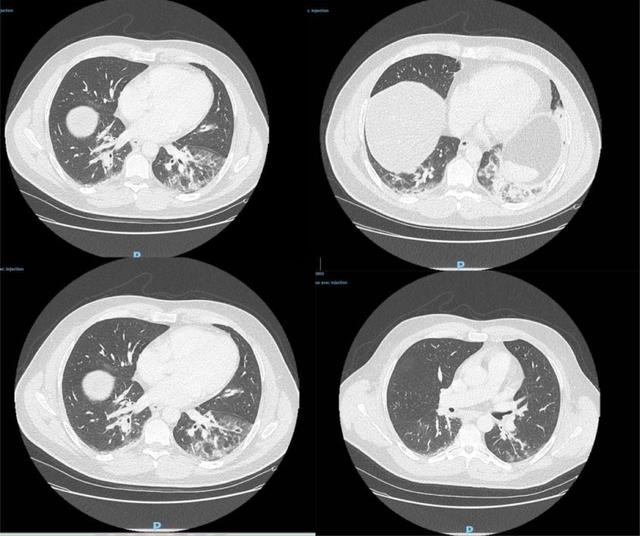

据了解,患者去年12月27日到急诊室就医,CT检查显示双侧肺下叶呈现磨玻璃影,并伴有咯血、咳嗽、头痛及发热症状,且当时症状已持续4天。病患当天被收入重症监护室并接受抗生素治疗,后因病情好转于12月29日解除重症监护。